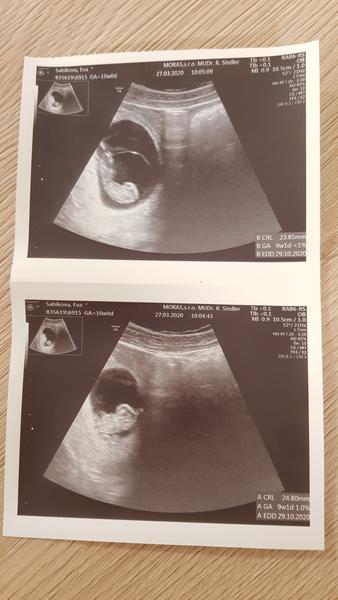

Čo vidíte na UTZ?

Ahojte čo myslíte dá sa z tejto fotky zistiť ci ide o jedno alebo dvojvaječné dvojičky? Sme v 5tt 🙂 prosím kto máte hoďte mi sem vaše fotky utz a aké dvojičky ste mali.. Jedno ci dvoj 🙂 ďakujem

Sú dvojvaječné 🙂 Jedovaječné by ešte nebolo vidieť v 5tt. My máme jednovajky a boli vidieť až vcca v 12tt na UTZ 🙂

Aspoň si myslím, že je to tak 😀 A jednovajky by asi boli v jednej dutinke.

Dvojvajecne. Jednovajecne by v takom štádiu ešte "neboli rozdelené". A také by pravdepodobne boli spolu v jednom vaku.

@nataliavlc to vyzera na biochorialne biamnialne...cize dvojvajecne. Mam to tak isto 🙂 uz som skoro 18.tt. je to prve tehu? Drzim palce nech je vsetko ok

@nataliavlc ja som mala takto a boli jednovajecne. Jedna placenta a dva obaly 🥰 krasna foto

Ahoj, toto budú skôr dvojvaječné, moje bolo vidieť dve fazuľky v jednom obale spolu, predsa len to vajíčko sa rozdelí na 2 časti, takze pri jednovajecnych sú spolu v jednom plodovom obale. Tu sú od seba vzdialene